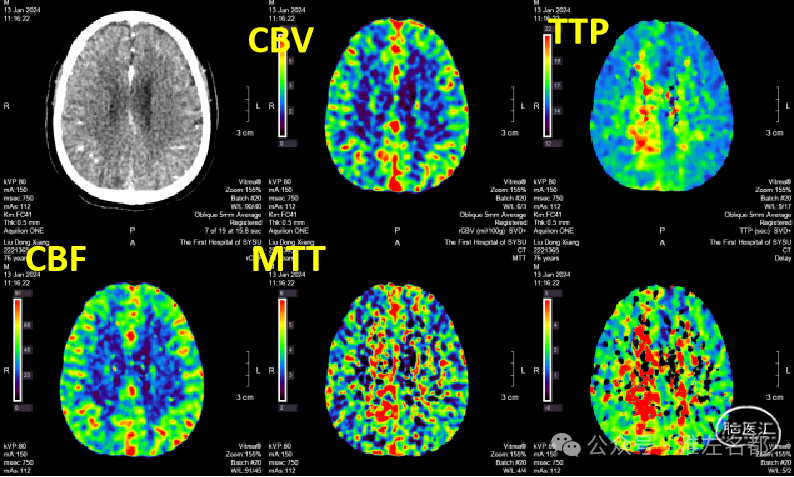

2024-01-13 11:34

急诊多模式CT

CT平扫:未及明确异常。

颅脑CTA:右侧大脑前动脉A2段局部管腔严重狭窄,右侧大脑前动脉A1段未发育,左侧大脑前动脉A1段粗大。

颈部CTA:所见脑供血动脉未见明确异常。

脑CTP:右侧大脑前动脉供血区局部TTP延长,相应区域CBF和CBV未见明显异常。